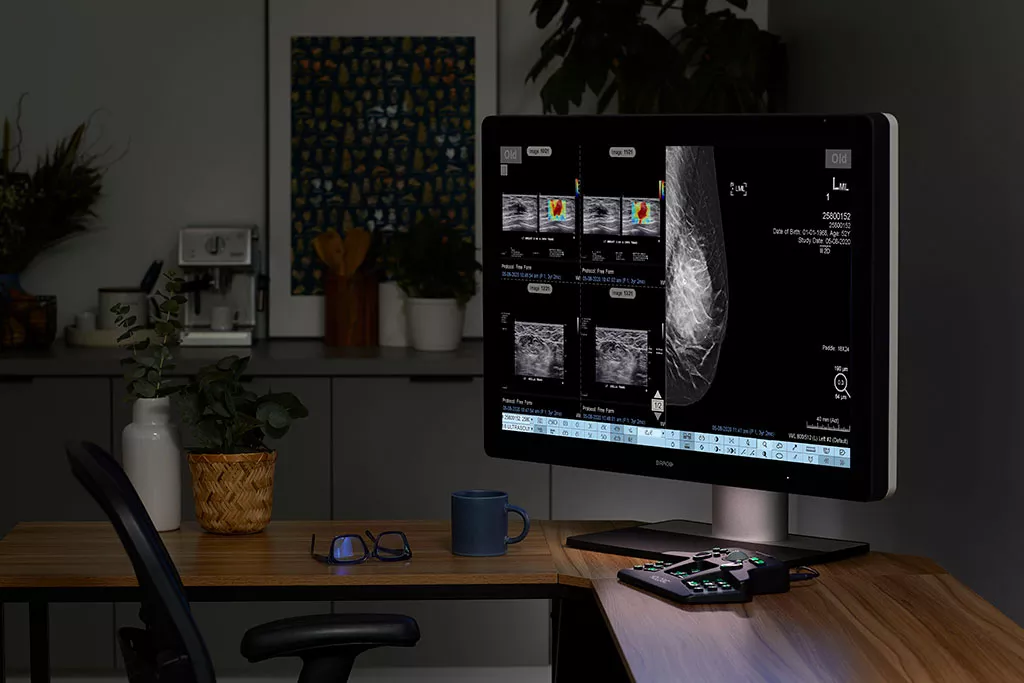

SecurView 12.0 is a multimodality solution with integrated ultrasound viewing and interpretation capabilities built directly in the SVDX viewer.

The system features accelerated image retrieval speeds for both current and prior studies for immediate review and fast, informed diagnostic decisions.

Includes Smart Breast Ultrasound Viewing

Breast ultrasound viewing capabilities included directly in the viewer application, including new features such as mosaic tiling and ultrasound measurements.

All relevant 2D and 3D™ breast ultrasound studies, including priors, are available for immediate review and diagnosis.